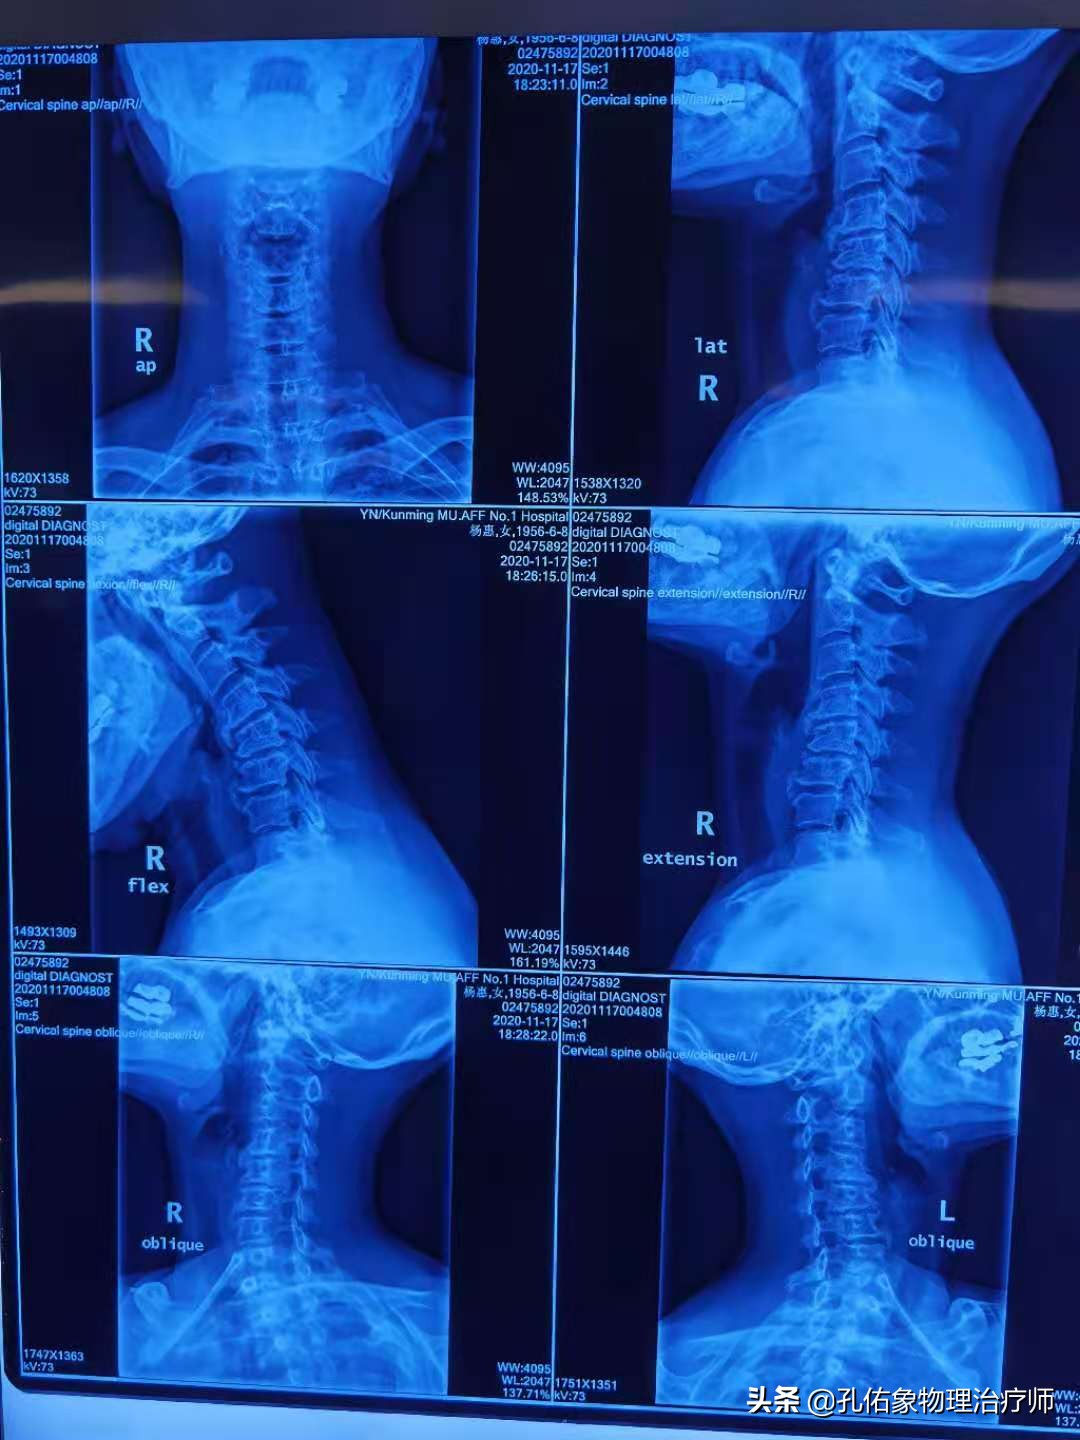

如上图所示,颈椎关节失稳后,会卡压其中穿行的神经,引起肩周疼痛(主要是肩的后外侧),肩背沉重疼痛、冷感;一般多见于C5-6,C6-7的椎间关节紊乱,若是在触诊时,会发觉关节突隆起、棘突和横突偏歪,在C5-6横突的前后方、冈上肌、大小圆肌、后斜角肌处有明显压痛,可以在肩胛骨内侧缘听到活动时的骨擦音。